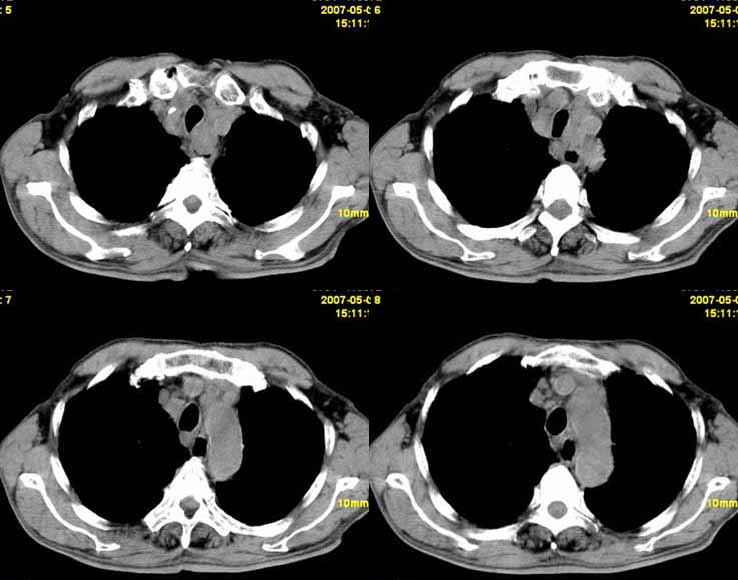

以下是引用小初学者在2007-5-12 11:09:00的发言:[br][br]双肺弥漫性质纤维化(考虑矽肺所致),并发左肺下叶背段周围性肺癌纵隔淋巴转移。

以下是引用zhangzhongshou在2007-5-12 12:09:00的发言:[br]1、左下叶背段周围型肺癌左肺门及纵隔淋巴结转移可能性大。[br]2、弥漫性肺气肿(双侧)。[br]3、双肺间质纤维化。

以下是引用老爱克斯新网客在2007-5-12 12:54:00的发言:[br]1周围型肺癌纵隔肺门淋巴结转移,2肺间质纤维化,